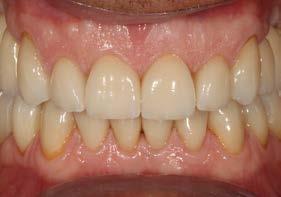

Explantación atraumática y recambio de implantes mal posicionados y afectados por periimplantitis sumado a la utilización de implantes estrechos y cortos. Enfoque mínimamente invasivo de un caso de atrofia ósea moderada

42 | INVESTIGACIÓN CLÍNICA